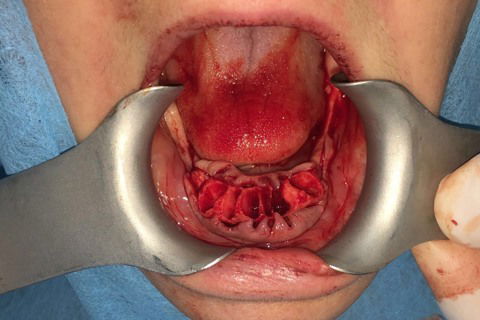

Paciente com síndrome de kelly,foi feito exodontia do 33 ao 43,regularização da tábua óssea e colocação de 5 implantes Implacil UN2 cônicos HI de 4x12,em seguida foi feito procedimento protetitico.

Fotos do caso